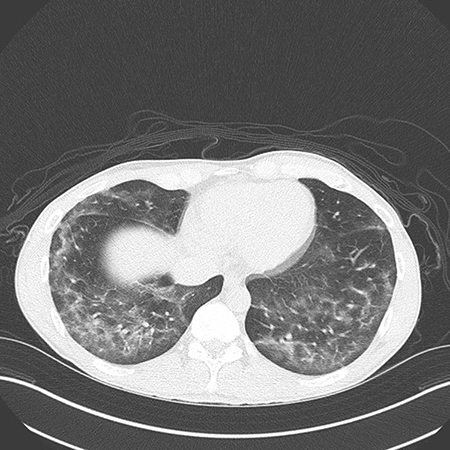

Clinical History: A young man in his 20s presented with fever, nausea, dyspnea and dry cough for 5 days. On examination, he was febrile and hypoxic on room air. Chest CT showed bilateral ground-glass opacities with areas of consolidation and some degree of subpleural sparing (Figure 1). Laboratory work-up showed leukocytosis, elevated ESR and elevated C-reactive protein. The patient was well prior to onset of these symptoms, with no significant chronic medical issues. There was no history of HIV/AIDS or other immunosuppression. The patient “smoked weed” daily and also vaped tetrahydrocannabinol (THC) frequently, the last episode being 7 days prior to onset of his symptoms. He was initially treated for presumed pneumonia but after a lack of response to treatment (and negative serologies and cultures), bronchoscopy with bronchoalveolar lavage (BAL) and transbronchial lung biopsies was performed. The BAL fluid revealed predominantly macrophages (Figure 2) without large or coarse vacuoles. Cultures of the BAL fluid were negative. Images from the transbronchial lung biopsy are shown in Figures 3-6.